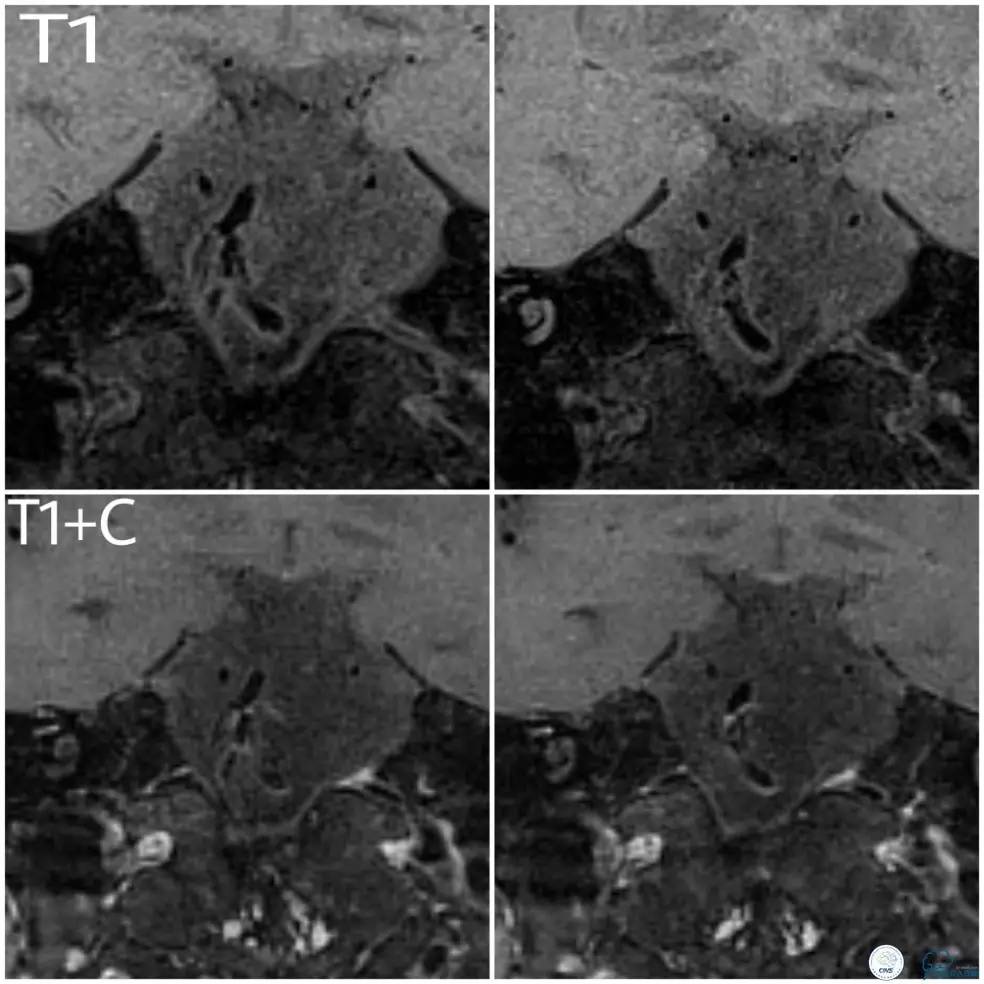

入院后查高分辨核磁提示(图4):基底动脉起始处管腔内壁环形增厚,斑块形成,内壁粗糙,形态不规则,斑块呈等T1信号,增强后斑块呈明显均匀强化。DWI序列上未见明显弥散受限病灶。考虑诊断基底动脉起始处管壁斑块形成,表面溃疡形成。

图4